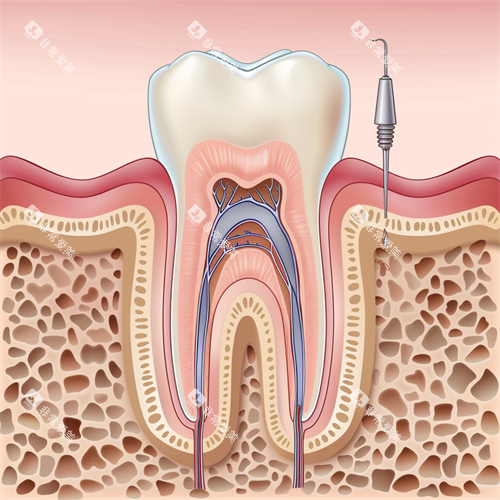

根管治疗:后牙多根管治疗费用可达3000元,显微镜下操作提高成功概率,技术附加值显著提升成本。